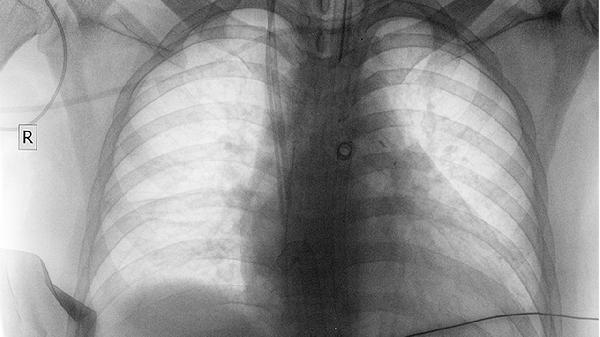

建议先到呼吸科做基础筛查,包括胸片和肺功能检测。不要自行判断为关节炎或皮肤病而延误检查。

早期肺癌可能仅有这些体表征兆,而没有任何呼吸道症状。每年低剂量CT筛查对高危人群尤为重要。